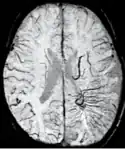

Sturge–Weber disease

An SWI venogram of a neonate with Sturge–Weber syndrome who did not display neurological symptoms is shown to the right. The initial conventional MR imaging methods did not demonstrate any abnormality. The abnormal venous vasculature in the left occipital lobe extending between the posterior horn of the ventricle and the cortical surface is clearly visible in the venogram. Due to the high resolution even collaterals can be resolved.